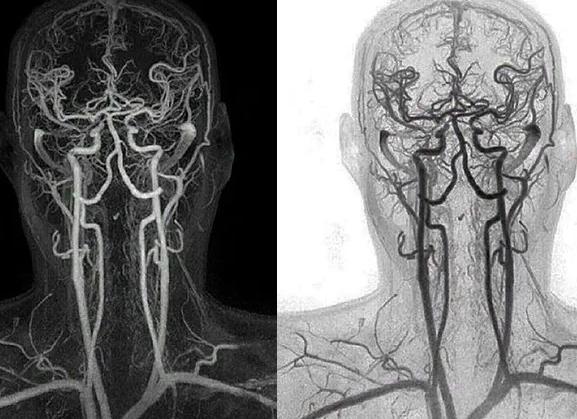

Существует и такая разновидность обследования, как КТ-ангиография головного мозга, при которой перед диагностикой в организм вводится контрастное вещество. В отличие от обычной томографии, КТ с контрастом позволяет подробно исследовать сосуды головного мозга и назначается для диагностики сосудистых заболеваний, нарушений кровообращения, а также новообразований. В свою очередь, КТ-ангиография подразделяется на венографию и артериографию, в зависимости от типа изучаемых сосудов.

Исследование сосудов головного мозга

Для изучения сосудов головного мозга используется КТ-ангиография. Для проведения процедуры вводится внутривенно контрастное вещество, как правило, содержащее йод. По распространению контраста в сосудах, врач-рентгенолог оценивает клиническое состояние кровеносной системы мозговой ткани и его оболочек. При таком виде исследования можно выявить атеросклеротические поражения сосудов, тромбоэмболические состояния, а также тромбозы вен и артерий.

КТ ангиография – основная область применения контрастного варианта исследования. С помощью ангиографии можно получить трехмерное изображение артерий и вен. В ходе исследования применяются технологии компьютерного 3D моделирования и реконструкции.

С помощью ангиографии можно выявить такие патологии:

• Закупорка сосудов тромбом.

• Расслоение артерий.

• Аневризма артерий, когда участок сосуда выпячивает, создается кармашек, из-за чего нарушается местный кровоток.

• Атеросклероз сосудов головного мозга.